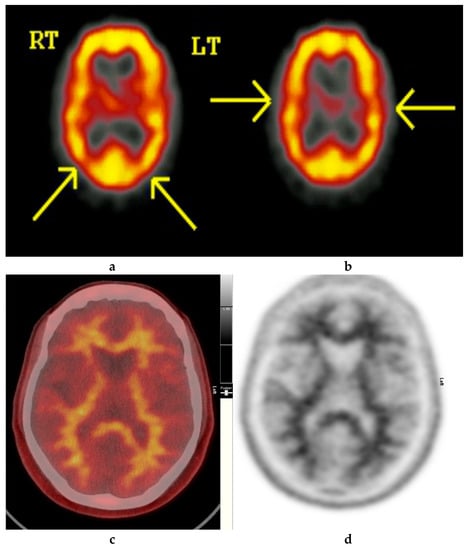

Figure 2.

Normal study. Fifty-seven year old female patient memory problems/loss and confusion with a query of Alzheimer’s disease. (a) and (b) Technetium-99m HMPAO-SPECT brain Scan [99mTc]HMPAO-SPECT brain scan. Brain scan showed mildly reduced perfusion to both temporal and both parietal lobes (yellow arrows) with relatively better perfusion anteriorly. Reduction of cerebral blood flow in these regions is commonly seen in patients with early Alzheimer’s dementia rather than vascular dementia. However, in view of the subtle nature of the appearances on the [99mTc]HMPAO-SPECT brain scan, the [18F]FBP brain scan was performed to identify beta amyloid plaque disease and to give a higher confidence for AD diagnosis or suggest vascular aetiology. (c) Color coded [18F]FBP scan. (d) Grey scale [18F]FBP scan shows good contrast between grey and white matter in sections of the brain and no obvious evidence of beta amyloid plaque disease. This means that the likelihood of developing AD is low and as such the overall findings are more suggestive of vascular aetiology rather than early AD. (Figures are courtesy RLBUHT Hospital database).